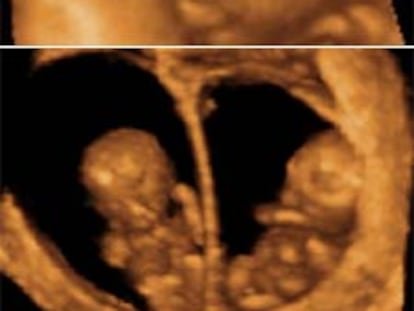

Ecografía en cuatro dimensiones